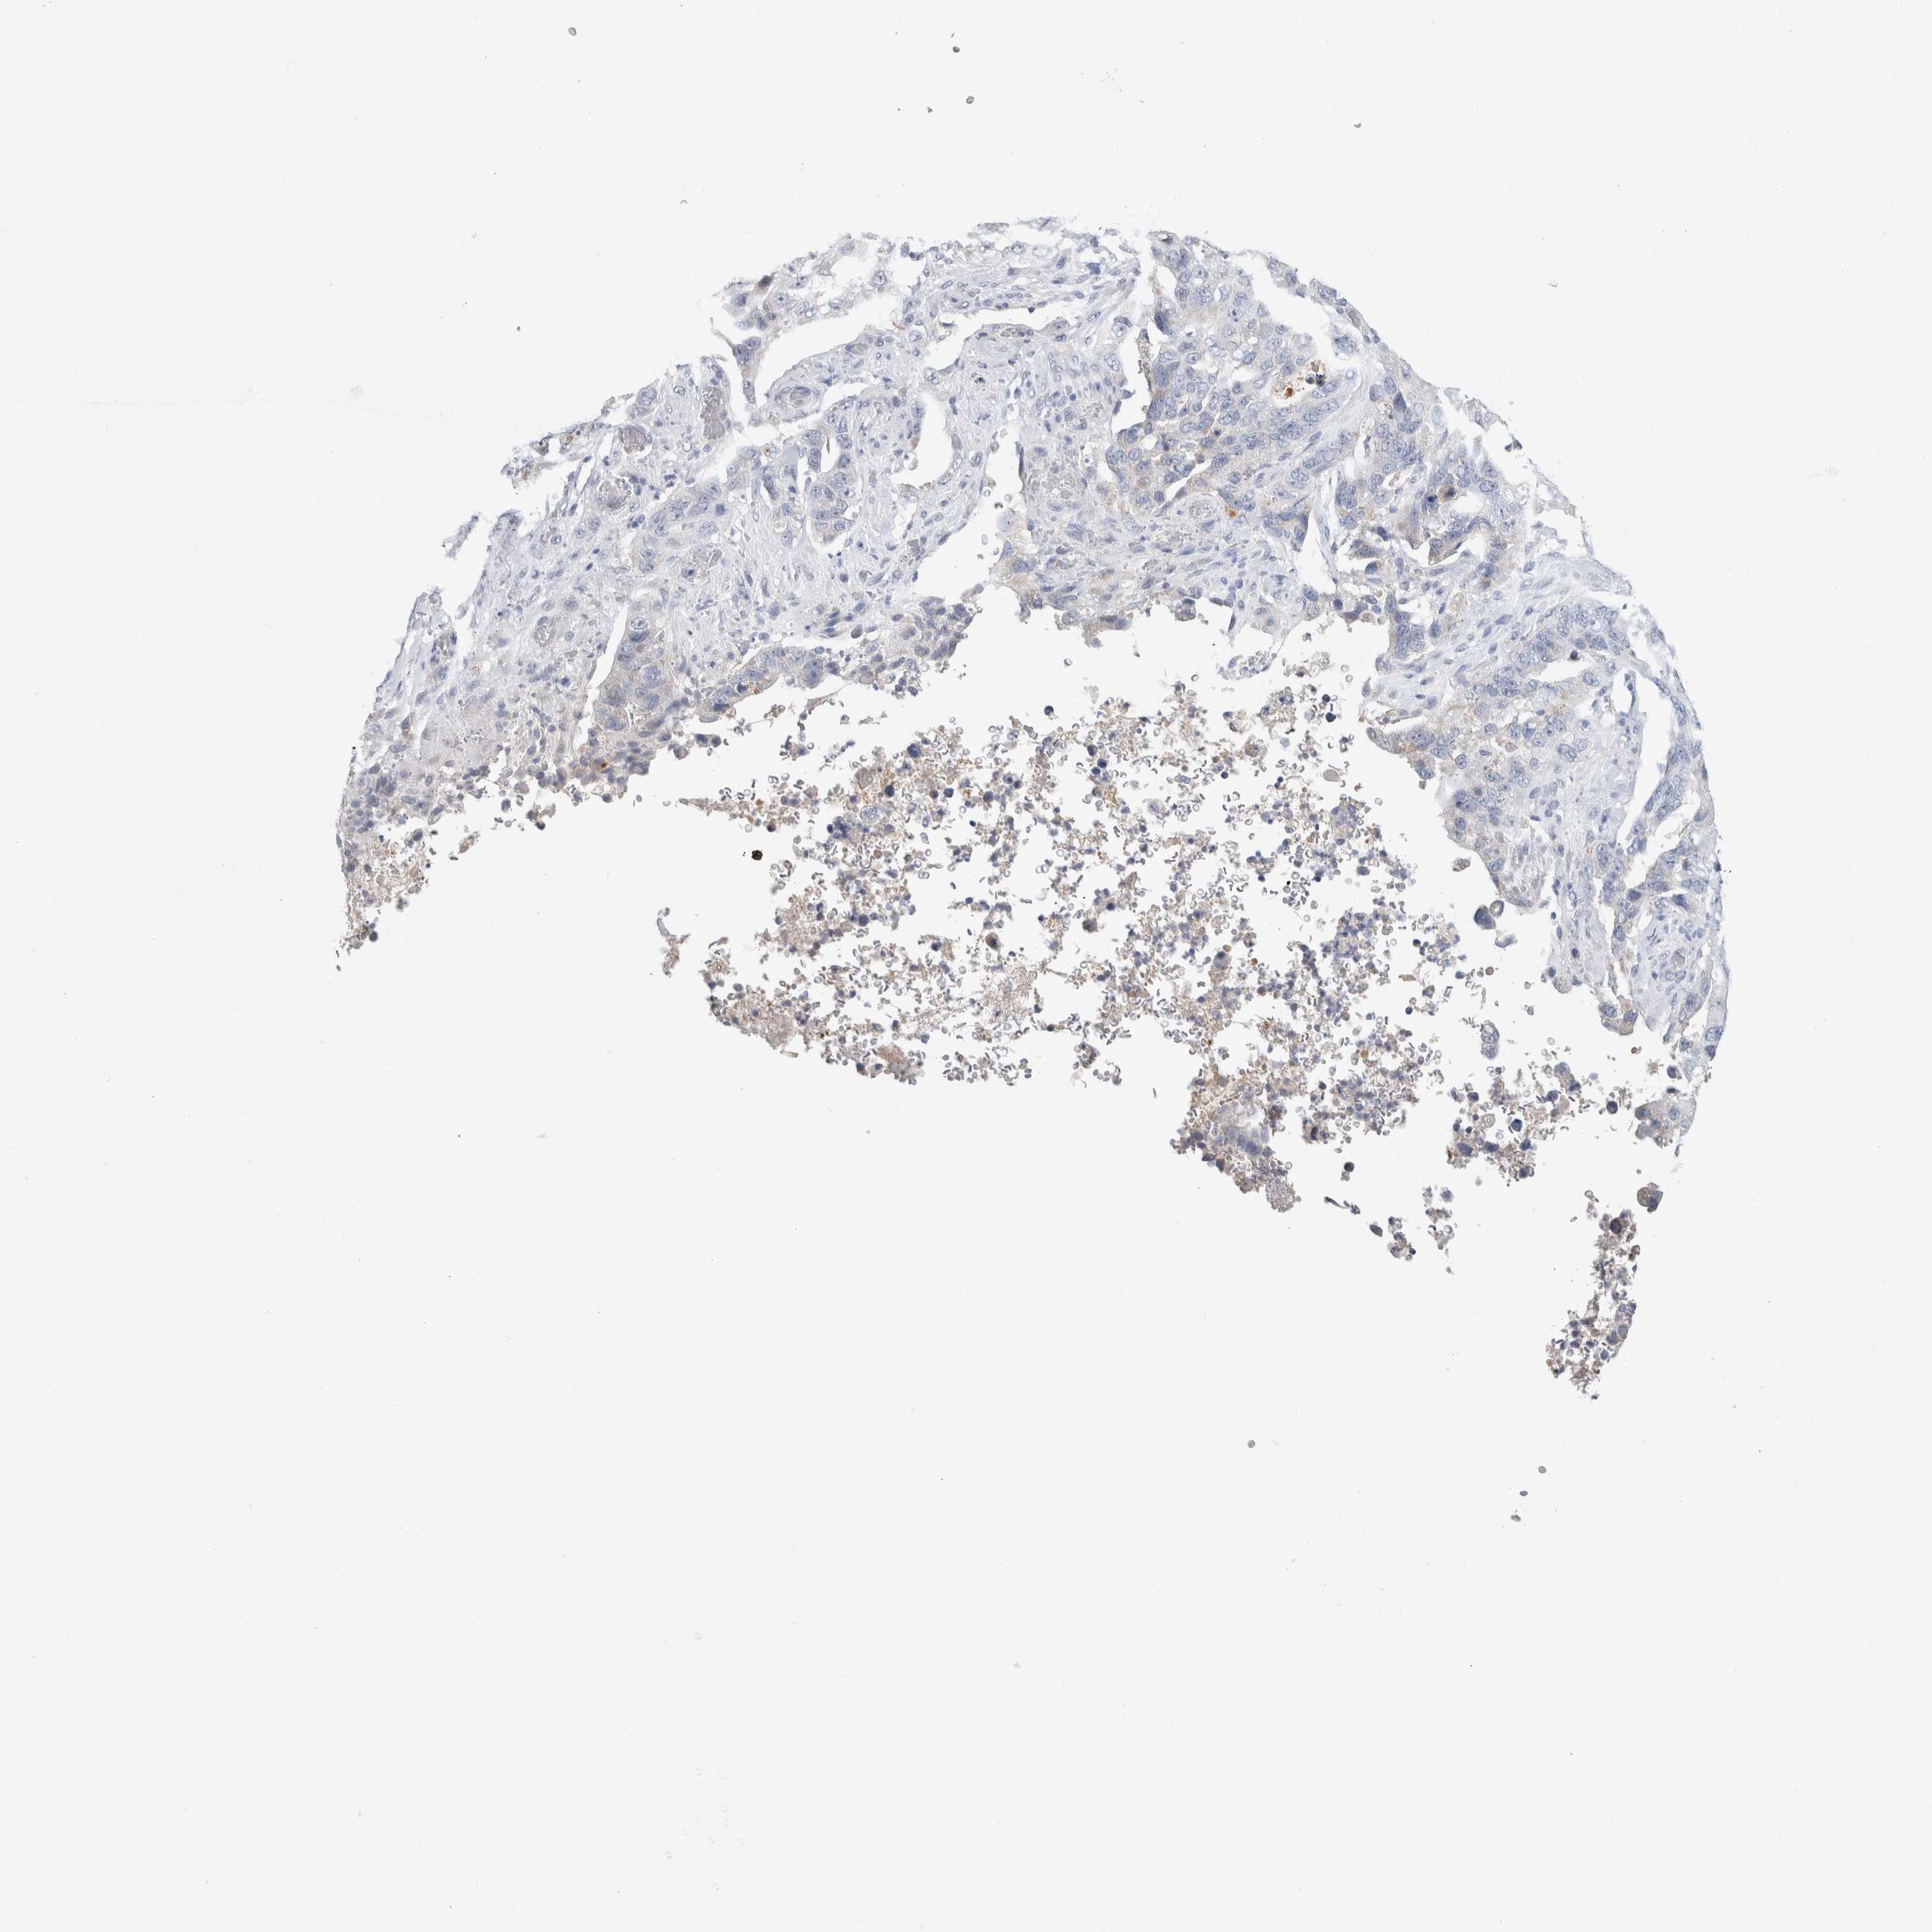

STOMACH CANCER - Protein expressioni

A mouse-over function shows sample information and annotation data. Click on an image to view it in a full screen mode. Samples can be filtered based on level of antibody staining by selecting one or several of the following categories: high, medium, low and not detected. The assay and annotation is described here.

Antibody stainingi

Antibody staining in the annotated cell types in the current human tissue is reported as not detected, low, medium, or high, based on conventional immunohistochemistry profiling in selected tissues. This score is based on the combination of the staining intensity and fraction of stained cells.

Each image is clickable and will lead to virtual microscopy that enables deeper exploration of all samples and also displays staining intensity scores, fraction scores and subcellular localization as well as patient and tissue information for each sample.

Antibody HPA031828

Antibody CAB025686

Staining

High

Medium

Low

Not detected

Intensity

Strong

Moderate

Weak

Negative

Quantity

>75%

75%-25%

<25%

None

Location

Nuclear

Cytoplasmic/membranous

Cytoplasmic/membranous,nuclear

Adenocarcinoma, NOS

Adenocarcinoma, High grade